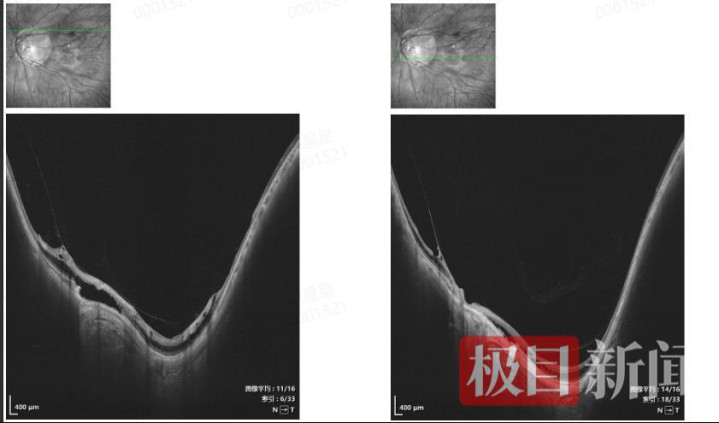

经看重查验,吴先生右眼裸目击识为0.02,戴镜改动认识为0.5;左眼裸目击识为0.02,戴镜改动认识却独一0.1。扫频OCT查验进一步显现,他的右眼黄斑部神经上皮层内有低反射暗腔,呈桥样聚首;左眼黄斑部网膜名义可见中高反射光带,与网膜呈牵拉状,神经上皮层内及层下见低反射暗强,部分呈桥样聚首。邢怡桥进一步查验后示意,吴先生是因高度近视引起的双眼视网膜劈裂症,其左眼病情更为严重需要手术治疗,而其右眼因为高度近视左近有变性区,需要择期进行衰弱性激光治疗,以幸免进一步泄漏为视网膜裂孔或视网膜零碎等严重并发症。

邢怡桥教训先容,视网膜劈裂是高度近视常见的眼底并发症,因眼轴过度拉长导致视网膜变薄,进而激发视网膜神经上皮层的层间隔离。中枢惩办原则是按期不雅察、戒指泄漏,必要时通过医疗技艺搅扰以防备认识进一步损害。吴先生的左眼病情已累及黄斑,必须通过手术切除玻璃体,剥出劈裂区内界膜,才智复原黄斑浅薄样式,防碍认识进一步着落;右眼则需择期进行激光治疗。邢怡桥教训为吴先生奏效扩充了左眼后入路玻璃体切割术,当今吴先生的病情踏实,正在徐徐复原。